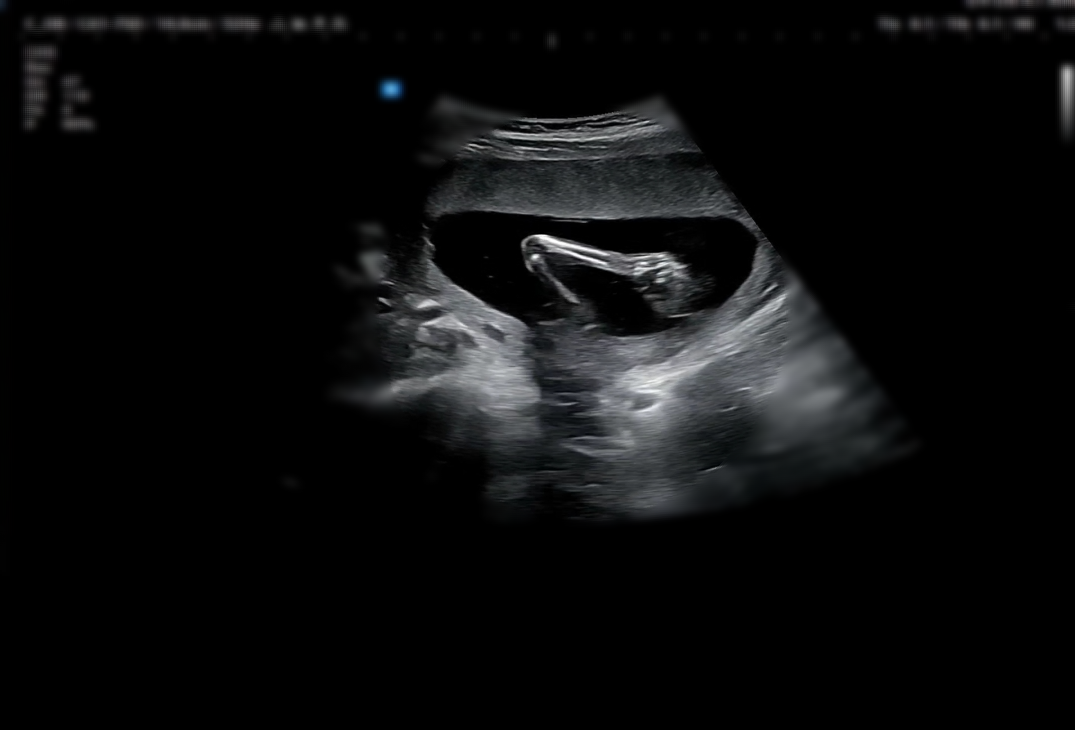

처음으로 배로 보는 초음파와 함께

1차 기형아 검사를 진행했고

목 투명대도 괜찮고 콧대도 잘 보인다고 했지만....

시험관을 해서 그런지 걱정이 많아서

비싸지만 NIPT 검사로 진행하였다